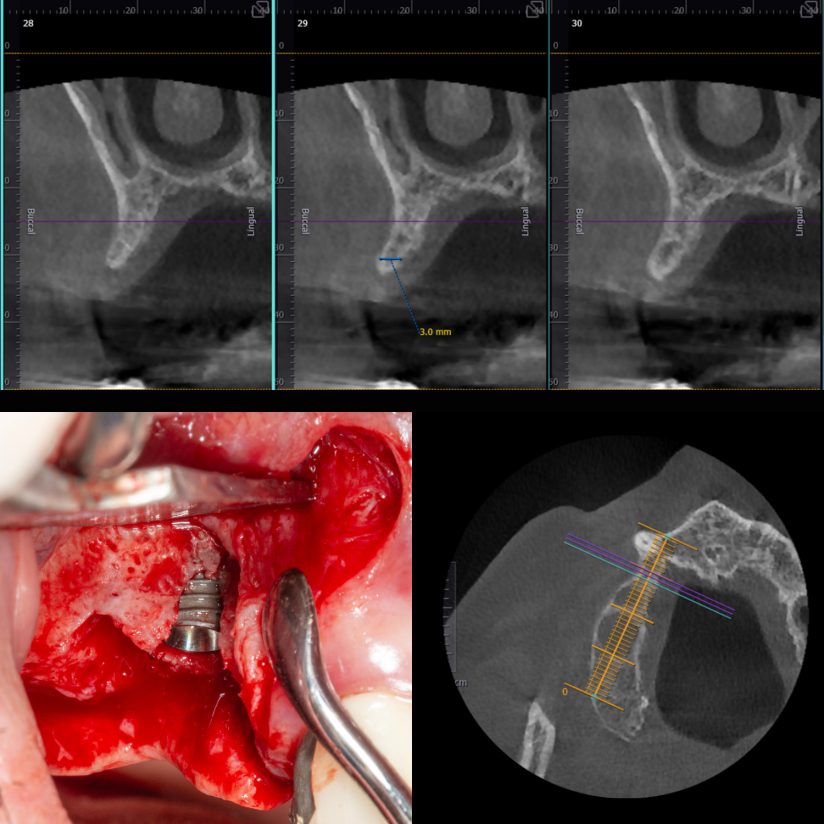

İmplant etrafındaki kemik açıklığını kemik grefti ile tedavi ettiğimiz vakamız.